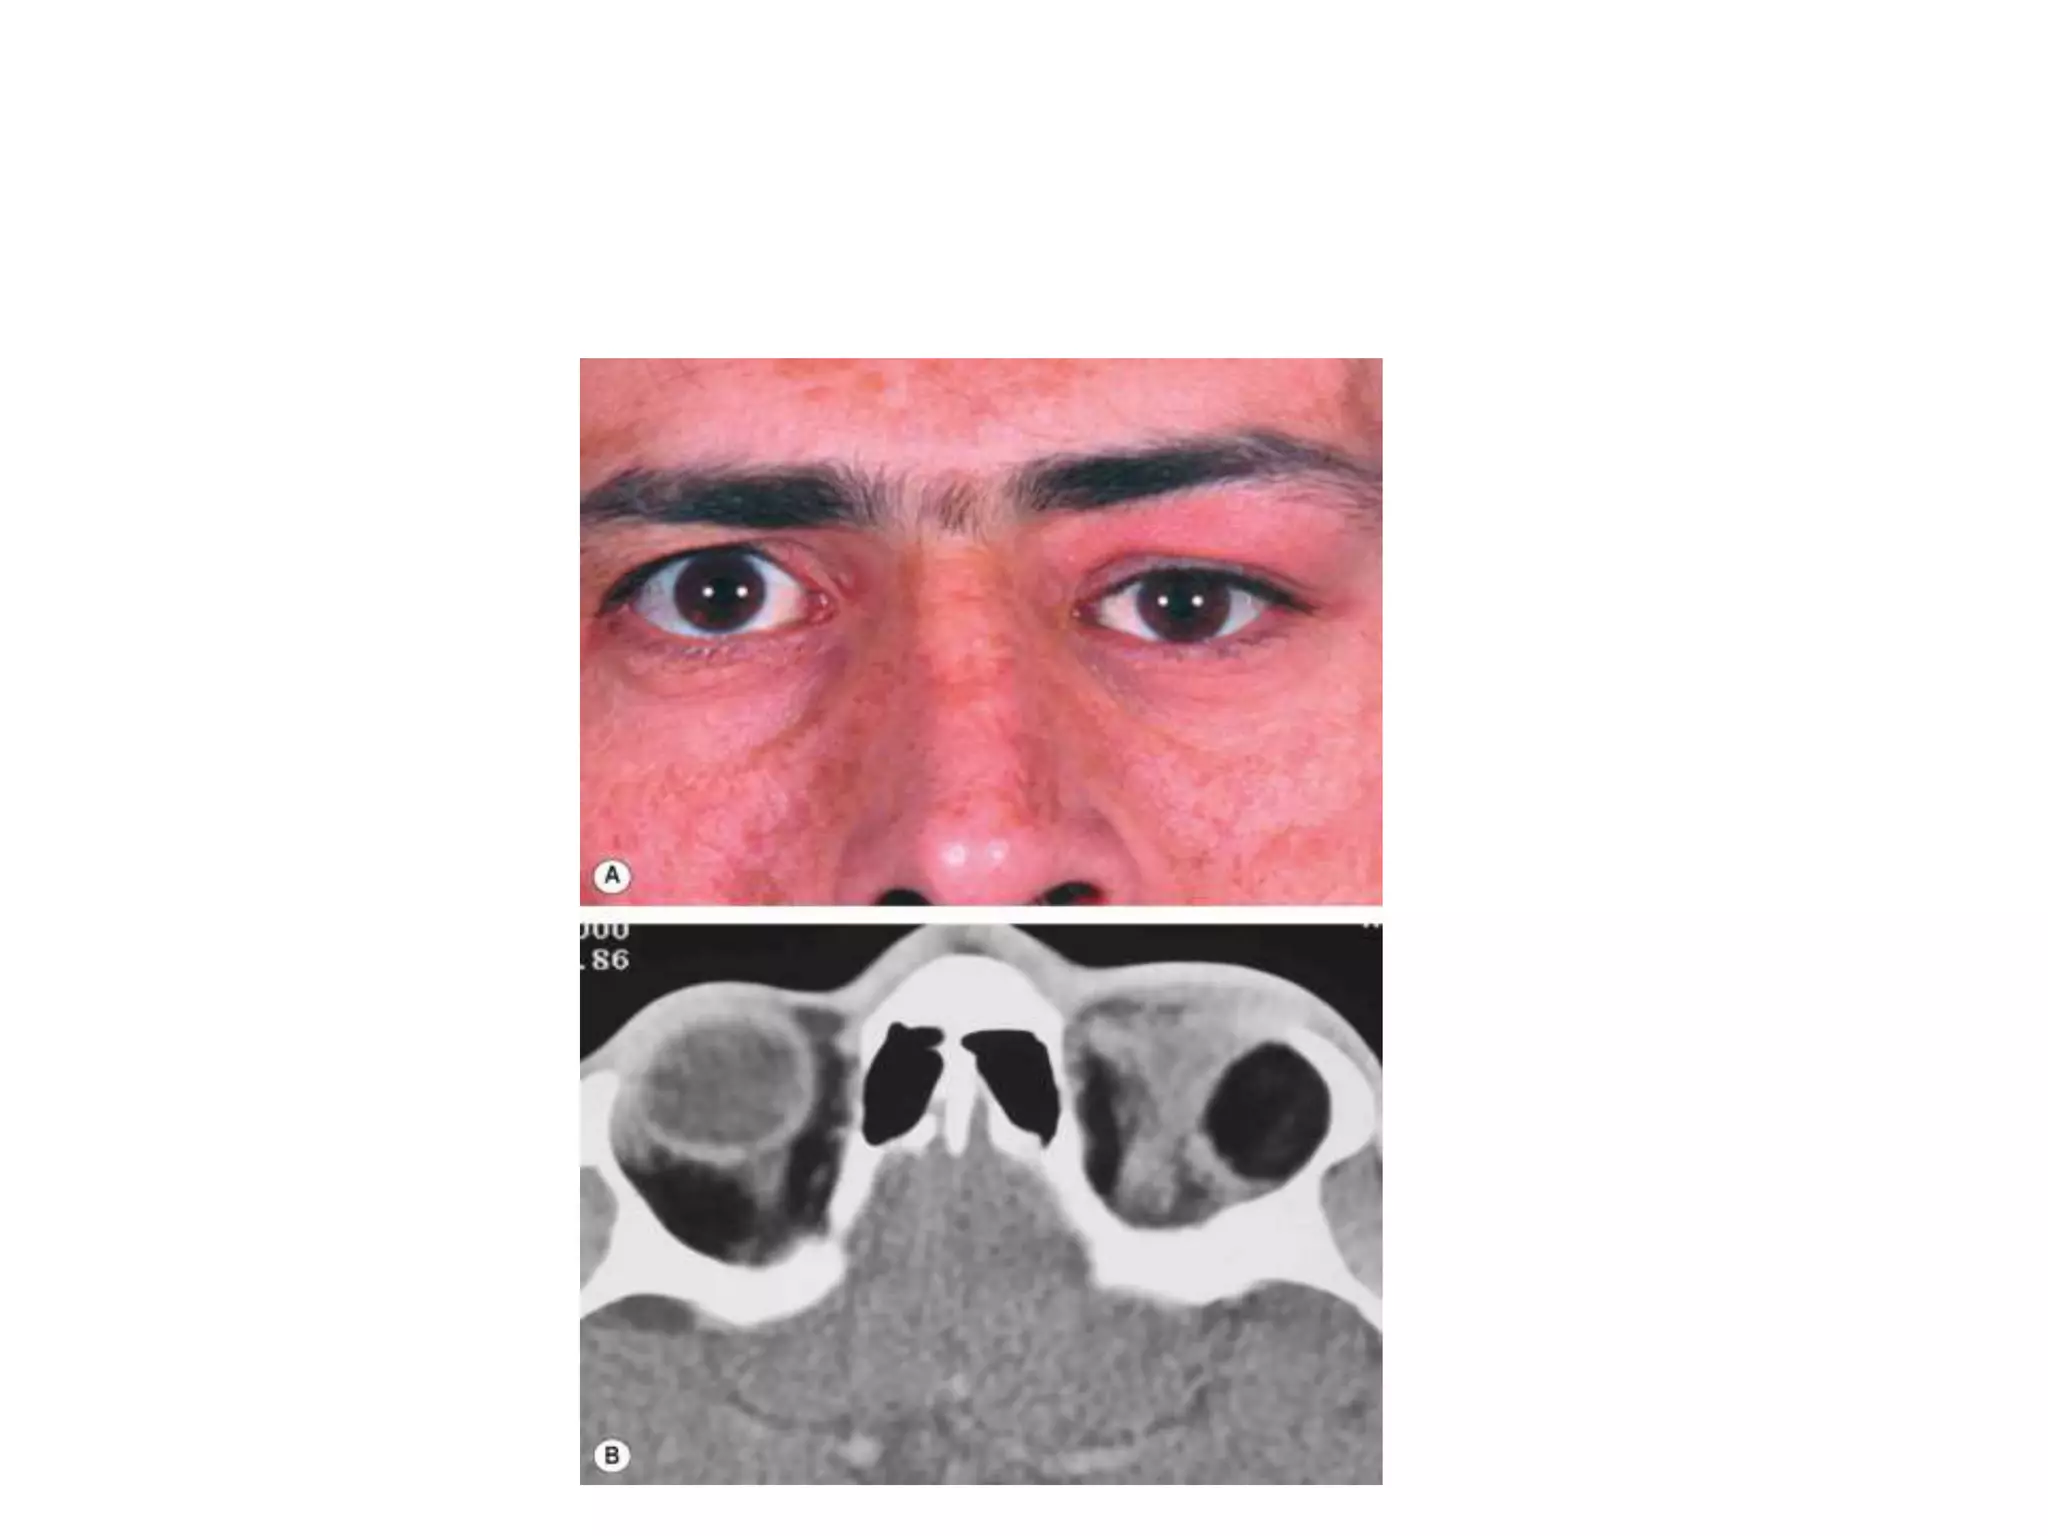

SINUS MUCOCELE

• A mucocele develops when the drainage of normal

para-nasal sinus secretions is obstructed due to

infection, allergy, trauma, tumour or congenital

narrowing.

• A slowly expanding cystic accumulation of mucoid

secretions and epithelial debris develops and

gradually erodes the bony walls of the sinuses,

causing symptoms by encroaching upon surrounding

tissues.

• Orbital invasion occurs usually from frontal or

ethmoidal mucoceles, and rarely from those arising in

the maxillary sinus.

• Presentation is in adult life with proptosis or

dystopia, diplopia or epiphora. Pain is uncommon

unless secondary infection develops (mucopyocele).

• CT shows a soft tissue mass with thinning or erosion

of the bony walls of the sinus (Fig. 3.28B).

• Treatment involves complete removal of the

mucocele.

SINUS MUCOCELE •A mucocele develops when the drainage of normal para-nasal sinus secretions is obstructed due to infection, allergy, trauma, tumour or congenital narrowing. • A slowly expanding cystic accumulation of mucoid secretions and epithelial debris develops and gradually erodes the bony walls of the sinuses, causing symptoms by encroaching upon surrounding tissues. • Orbital invasion occurs usually from frontal or ethmoidal mucoceles, and rarely from those arising in the maxillary sinus.

• 12.

• Presentation isin adult life with proptosis or dystopia, diplopia or epiphora. Pain is uncommon unless secondary infection develops (mucopyocele). • CT shows a soft tissue mass with thinning or erosion of the bony walls of the sinus (Fig. 3.28B). • Treatment involves complete removal of the mucocele.